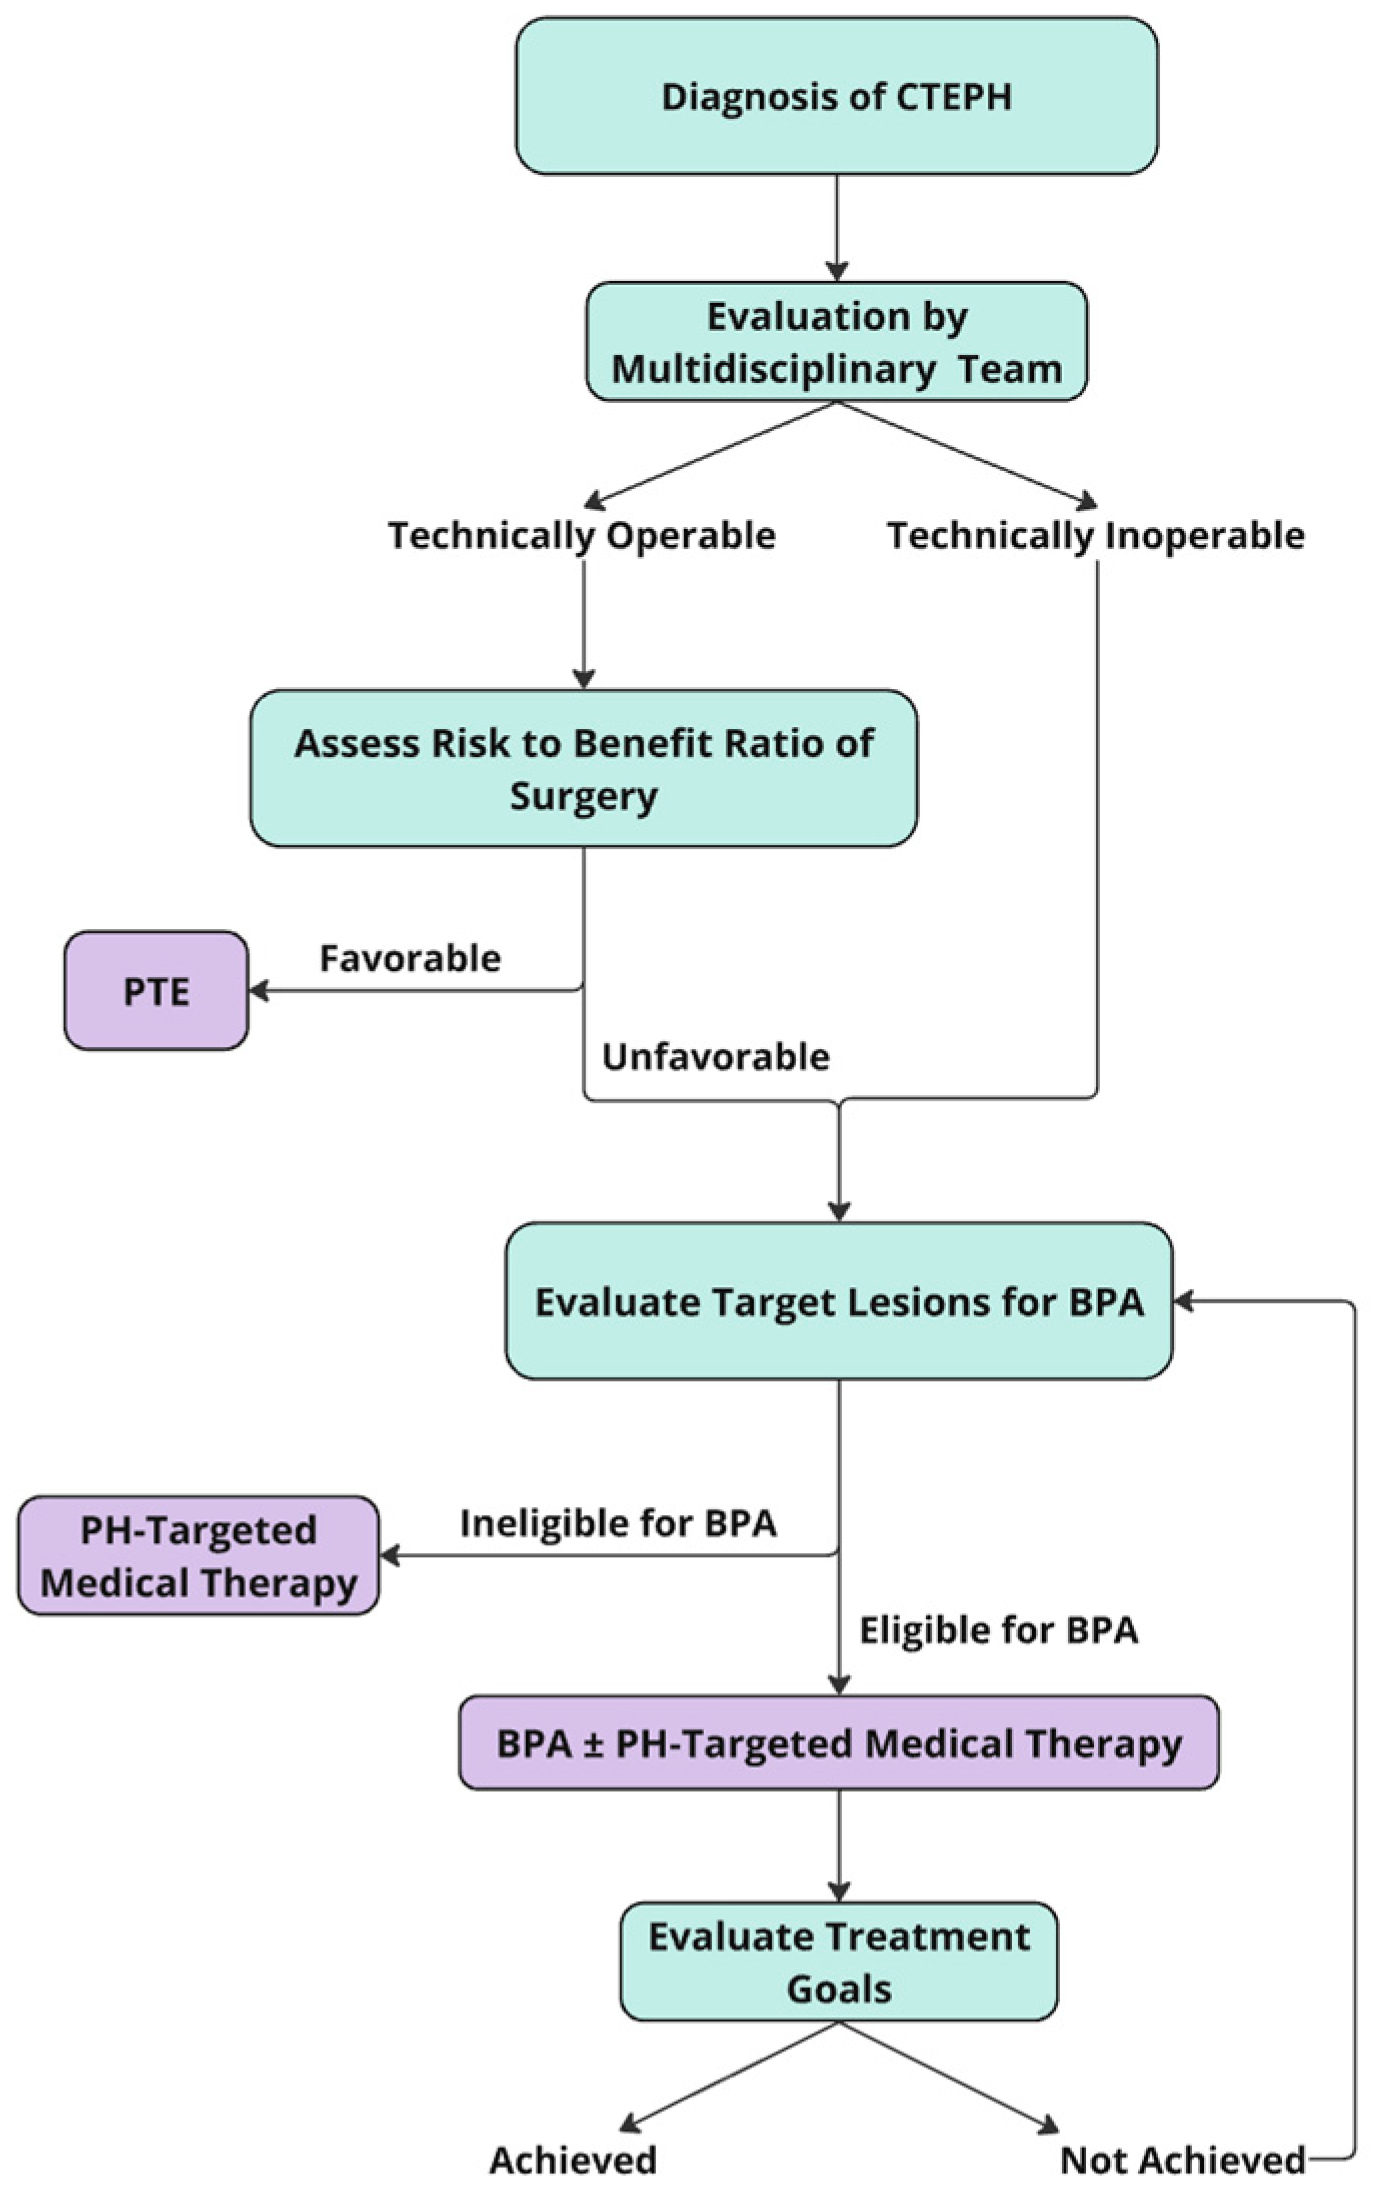

3. Catheter-Based Pulmonary Angiogram

4. Indications and Patient Selection for BPA